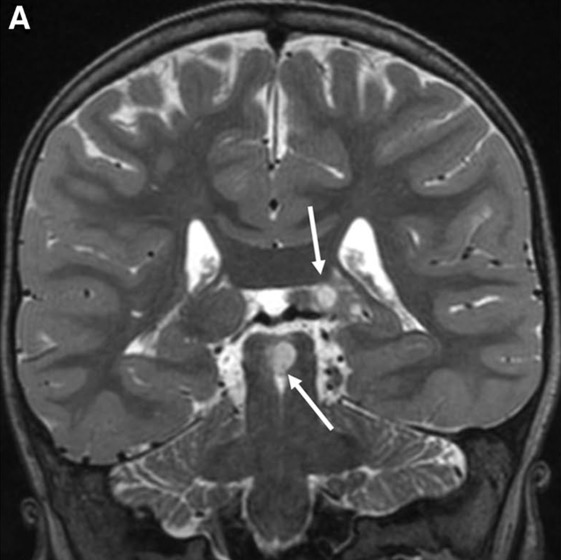

c. Lipomatose encéphalocraniocutanée (ECCL): peau, yeux, SNC)

ECCL: